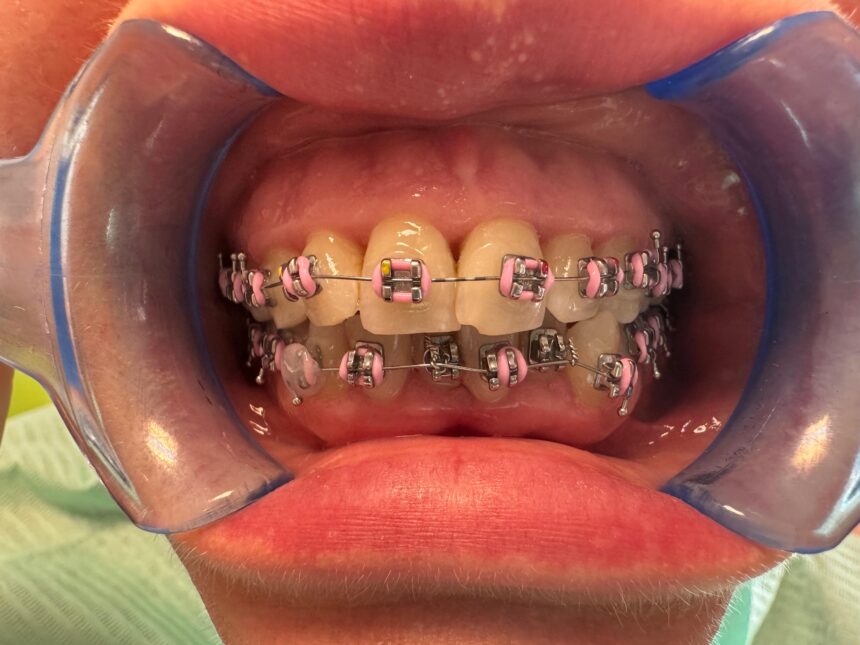

Ce tipuri de aparate aleg adulții?

„Adulții preferă, în general, variante cât mai discrete, precum aparatele ceramice, din safir sau alignerele transparente. Totuși, alegerea nu ar trebui să se bazeze exclusiv pe criteriul estetic. Complexitatea cazului și recomandarea medicului sunt esențiale”, subliniază specialistul.

În anumite situații, aparatul fix clasic oferă cel mai bun control al mișcărilor dentare, chiar dacă este mai vizibil.

Cât de importantă este colaborarea pacientului?

„La adulți, colaborarea este decisivă. Respectarea indicațiilor, prezentarea la controale și menținerea unei igiene orale riguroase influențează direct rezultatele și durata tratamentului”, spune medicul.